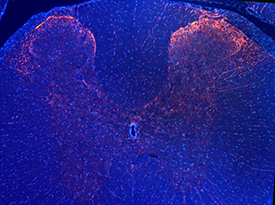

Images